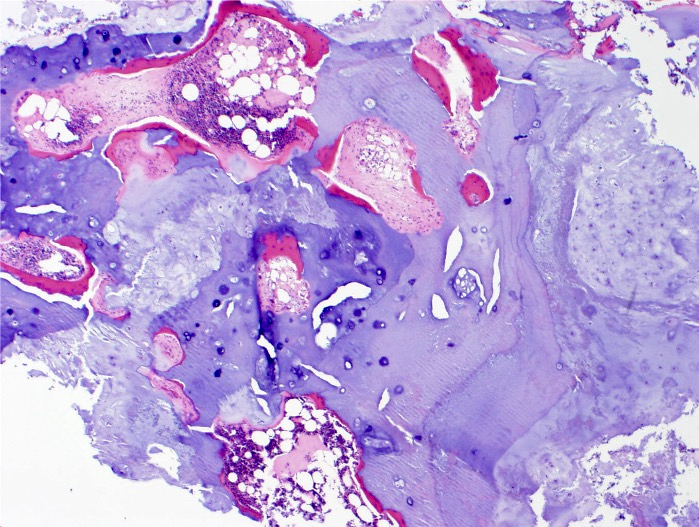

Microscopic (histologic) description

- Lobulated growth pattern (J Dent Res Dent Clin Dent Prospects 2011;5:98)

- Lobules have irregular shapes and sizes and may be separated by fibrous bands containing small vessels (Virchows Arch 2012;460:95)

- Lobules are composed of abundant hyaline cartilage matrix (sometimes with mucoid / myxoid changes) and permeate and entrap lamellar bone trabeculae

- Cellularity is slightly higher than in enchondroma

- Cells show moderate eosinophilic to vacuolated cytoplasm

- Nuclei are small and uniform with condensed chromatin (lymphocyte-like); sometimes they show open chromatin with visible nucleoli (Am J Surg Pathol 2009;33:50)

- Mitoses and significant nuclear pleomorphism are absent

- Binucleation can be observed

- Necrosis can be seen

- In cases arising from pre-existing enchondromas, areas of enchondroma with calcifications can be present

- In cases arising from pre-existing osteochondroma, evidence of this tumor can be seen (Mod Pathol 2012;25:1275)

Microscopic (histologic) images